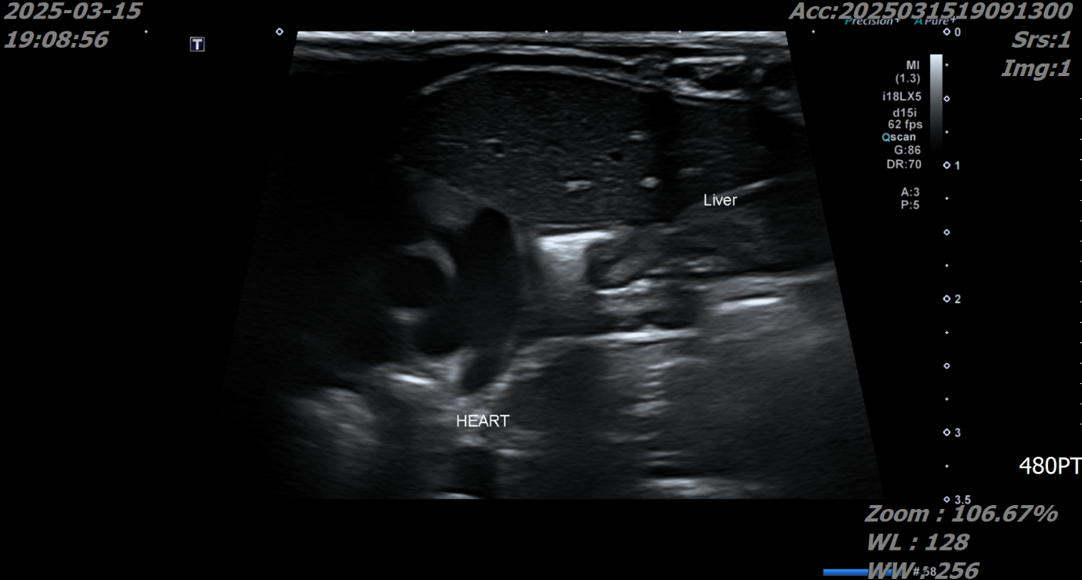

초음파 검사에서도 심장 옆 흉강 공간에서 간과 장이 발견되었으며 특히 간의 울혈이 확인되었습니다.

장기의 strangulation(혈행장애로 인한 허혈 상태)가 관찰되지는 않았으나 지속적인 호흡 곤란으로 긴급한 수술적 교정이 지시되는 상황이었습니다.